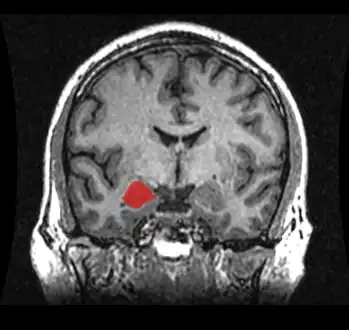

![]() Location of the amygdalae in the human brain | |

The amygdala (/əˈmɪɡdələ/; pl.: amygdalae /əˈmɪɡdəli, -laɪ/ or amygdalas; also corpus amygdaloideum; Latin from Greek, ἀμυγδαλή, amygdalē, 'almond', 'tonsil'[1]) is a paired nuclear complex present in the cerebral hemispheres of vertebrates. It is considered part of the limbic system.[2] In primates, it is located medially within the temporal lobes.[3] It consists of many nuclei, each made up of further subnuclei. The subdivision most commonly made is into the basolateral, central, cortical, and medial nuclei together with the intercalated cell clusters.[4] The amygdala has a primary role in the processing of memory, decision-making, and emotional responses (including fear, anxiety, and aggression). The amygdala was first identified and named by Karl Friedrich Burdach in 1822.[5]

Amygdala highlighted in green on coronal T1 MRI images